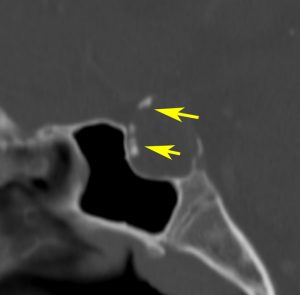

視神経への圧迫はとれたので,今度は腫瘍の本体を摘出しなければならないのですが,トルコ鞍上部に大きな骨化(黄色の矢印)があります。骨化は15mmくらいの大きさがありました。この大きな骨化は砕くことができずに,周囲を全部剥離して一塊にして引きずり出しました。後交通動脈の下側から引っ張りだしたのですが,かなり危険な手術操作でした。結果的には,下垂体柄を温存できて腫瘍を全摘出しました